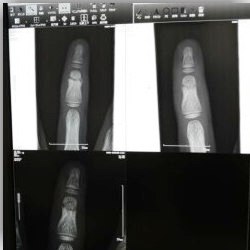

2歳にして骨折した前科もあるし、骨折再びか!?

レントゲン

で、翌日整形外科へ。

次男様、5年ぶりのレントゲンざます。

医者「ありゃ、これは骨折だ。固定だ!」

というわけで、指の形に沿う固定できるシートで固定。

全治一カ月。

まだ、治っておりません。

1ヶ月後の本日、まだ治っておりません。